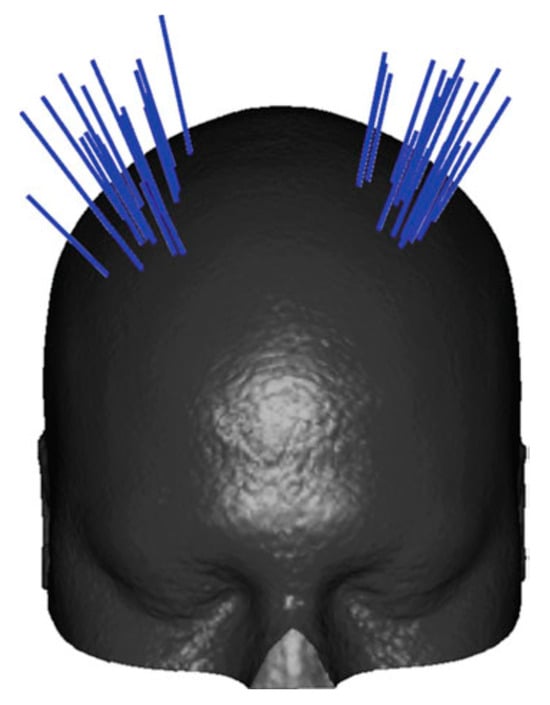

In Europe, there has been a multi-institutional endeavor, Enhanced Delivery Ecosystem for Neurosurgery 2020 project (EDEN2020), funded by the European Union’s Horizon 2020 research and innovation program (www.eden2020.eu, accessed on 9 May 2024), to develop a gold standard method for one-stop diagnosis and minimally invasive treatment in neurosurgery. They have developed a novel steerable needle that consists of four identical quadrants as shown in Figure 8. This biologically inspired steerable needle system, initially called STING, was proposed to tackle challenges associated with conventional needle steering systems, including tissue trauma, and to improve the workspace and applicability [,]. Pinzi et al. [] proposed a GPU-accelerated computer-assisted planning algorithm for steerable needle insertions.

Figure 8.

STING is made of 4 identical quarters (a), STING cross-section with interlocking mechanism is shown (b). Reprinted/adapted with permission from Ref. [].